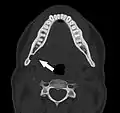

Stafne bone cavity seen on coronal CT

Stafne bone cavity seen on axial CT

Stafne's defect is usually discovered by chance during routine dental radiography.[11] Radiographically, it is a well-circumscribed, monolocular, round, radiolucent defect, 1–3 cm in size, usually between the inferior alveolar nerve (IAN) and the inferior border of the posterior mandible between the molars and the angle of the jaw. It is one of the few radiolucent lesions that can occur below the IAN. The border is well corticated and it will have no effect on the surrounding structures. Computed tomography (CT) will show a shallow defect through the medial cortex of the mandible with a corticated rim and no soft tissue abnormalities, with the exception of a portion of the submandibular gland. Neoplasms, such as metastatic squamous cell carcinoma to the submandibular lymph nodes or a salivary gland tumour, could create a similar appearance but rarely have such well defined borders and can usually be palpated in the floor of the mouth or submandibular triangle of the neck as a hard mass. CT and clinical exam is typically sufficient to distinguish between this and a Stafne defect. The Stafne defect also tends to not increase in size or change in radiographic appearance over time (hence the term "static bone cyst"), and this can be used to help confirm the diagnosis.[11] Tissue biopsy is not usually indicated, but if carried out, the histopathologic appearance is usually normal salivary gland tissue. Sometimes attempted biopsy of Stafne defects reveals an empty cavity (possibly because the gland was displaced at the time of biopsy), or other contents such as blood vessels, fat, lymphoid or connective tissues. Defects of the anterior lingual mandible may require biopsy for correct diagnosis at this unusual location.[5] The radiolucent defect here may be superimposed on the lower anterior teeth and be mistaken for an odontogenic lesion. Sometimes the defect may interrupt the contour of the lower border of the mandible, and may be palpable. Sialography may be sometimes used to help demonstrate the salivary gland tissue within the bone.